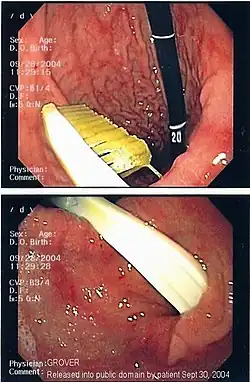

Knochensplitter oder Fischgräten können nach dem Verschlucken in die Schleimhaut des Schlunds oder der Speiseröhre eingespießt werden und dort zu Entzündungen führen. Verschluckte Fremdkörper, die in den Magen gelangt sind, gehen je nach Größe meist auf natürlichem Wege wieder ab. Bezoare (Trichobezoare, etwa eigene Haargeschwülste beim Menschen, und bei Tieren aus Pflanzenfasern gebildete Phytobezoare) können als Fremdkörper die Magen-Darm-Passage behindern.[1] Bei Knopfzellen wird die Entfernung aus dem Magen empfohlen, da eine Zerstörung der Hülle durch die Magensäure und ein Freiwerden giftigen Inhalts befürchtet werden muss. Grundsätzlich ist eine Entfernung bis in den oberen Dünndarm mittels Endoskopie möglich.